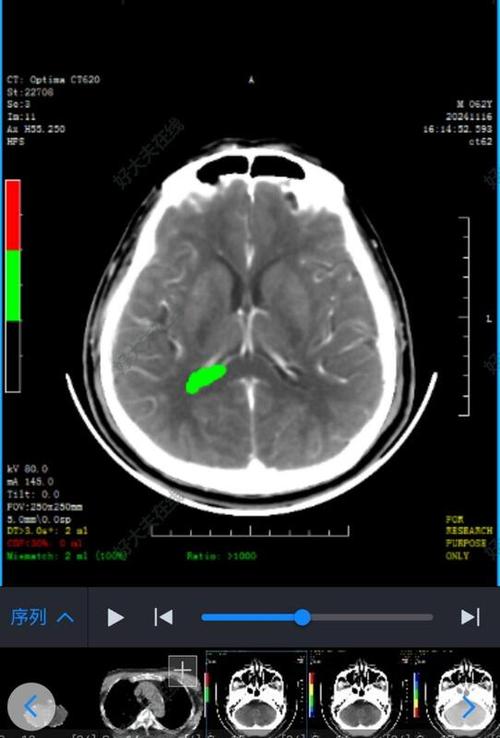

- 原理: 通过X射线探测不同组织的密度差异,脑梗塞早期脑组织密度变化不大,所以看不出来。

- 优点: 快速、便捷、价格低廉,能快速排除脑出血。

- 缺点: 对早期、轻微的缺血性病变不敏感。

- DWI序列(弥散加权成像): 这是诊断超早期脑梗塞的“金标准”,在发病几分钟到几小时内,缺血区域的细胞内水分移动受限,在DWI上会显示为明显的高信号(亮区),可以比CT早数小时甚至更早发现病灶。

- 对后循环梗塞更敏感: 脑干、小脑等部位的梗塞,CT有时难以显示,而MRI则非常清晰。